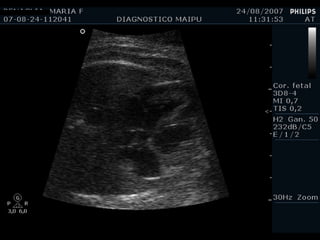

Flap

Septum